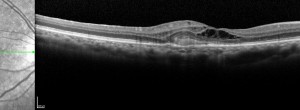

MANTRA: evaluación de la asociación entre la sensibilidad y el flujo retiniano en la DMAE

KODIAK: Estudio fase II en pacientes con DMAE forma exudativa.

Ensayo clínico TALON: Eficacia y seguridad de brolacizumab en el tratamiento de la DMAE exudativa

Ensayo clínico LUCERNE: Eficacia y seguridad de FARICIMAB respecto de aflibercept en el tratamiento de la degeneración macular asociada a la edad exudativa

VELODROME: eficacia, seguridad y farmacocinética de ranibizumab 100 mg/ml a través de un PDS en pacientes con nDMAE